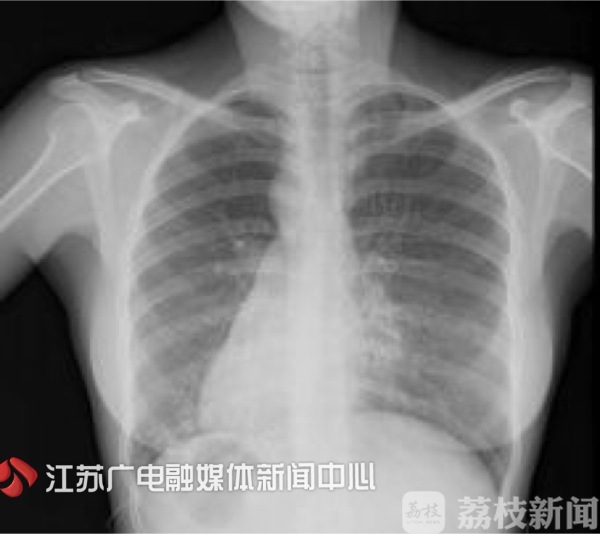

今年71岁的嵇女士,在十几岁体检时才得知自己的心脏和别人不一样,常人心脏在胸腔左侧,而她的心脏却长在右侧。虽然体内器官反位,但是并不会影响正常生活,直到四年前,嵇女士发现一运动就胸口闷、胸口痛。

经诊断,嵇女士患上了严重的冠心病,心脏右冠的近段和远段有90%的狭窄,一旦狭窄的血管完全堵塞,很有可能发生心肌梗死,甚至可能会出现猝死。最好的办法是及时为嵇女士进行冠状动脉介入手术,但是由于"右心人"是心脏的一种异常发育,概率仅为万分之一。医生必须针对患者的内脏转位特点,调整手术习惯、技巧、器材位置等,就好比照着镜子"反向操作"做手术。